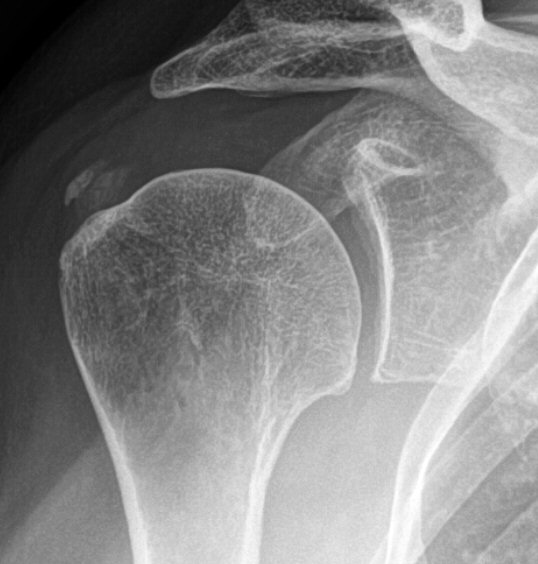

Två exempel på kalkaxlar, både med kraftig smärta och förhöjt CRP men återställda efter några dagar.

• Röntgenbild med typisk förkalkning i supraspinatussenan